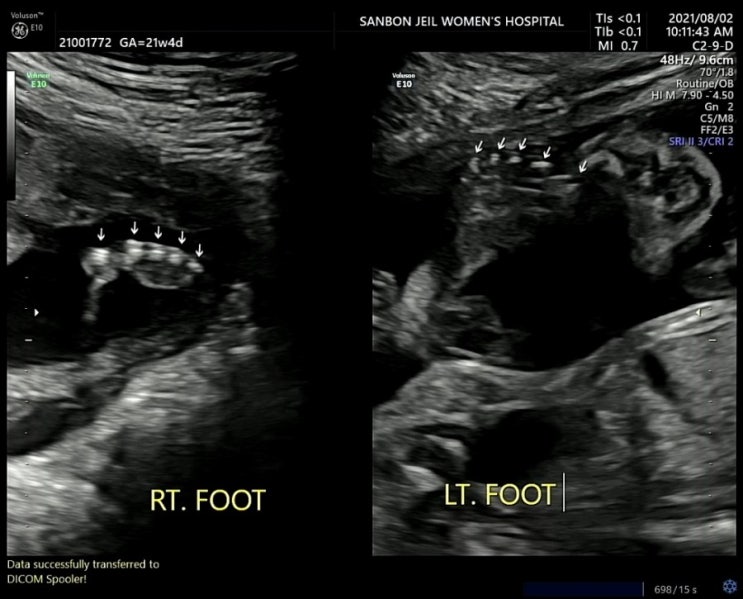

임신 20주~21주 : 입덧끝, 소화불량시작일까, 2차 정밀초음파, 폭풍태동 임신 6개월차